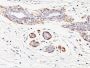

IHC, FFPE (verified)

Smooth muscle myosin heavy chain (SM-MHC) is a cytoplasmic structural protein, which is a major component of the contractile apparatus in smooth muscle cells. Expression of smooth muscle myosin is developmentally regulated, appearing early in smooth muscle development, and is specific for smooth muscle development. Two isoforms of smooth muscle myosin heavy chain have been identified, designated MHC-1 and MHC-2. The antibody may be useful for the study of breast tumors as the presence of an intact layer of myoepithelial cells is an important feature, which may distinguish benign breast lesions and carcinoma in situ from invasive tumors.Primary antibodies are available purified, or with a selection of fluorescent CF® Dyes and other labels. CF® Dyes offer exceptional brightness and photostability. Note: Conjugates of blue fluorescent dyes like CF®405S and CF®405M are not recommended for detecting low abundance targets, because blue dyes have lower fluorescence and can give higher non-specific background than other dye colors.

Uterus or normal breast

IHC (FFPE) (verified)

Higher concentration may be required for direct detection using primary antibody conjugates than for indirect detection with secondary antibody|Immunofluorescence: 0.5-1 ug/mL|Immunohistology formalin-fixed 0.5-1 ug/mL|Staining of formalin-fixed tissues requires boiling tissue sections in 10 mM citrate buffer, pH 6.0, for 10-20 min followed by cooling at RT for 20 minutes|Flow Cytometry 0.5-1 ug/million cells/0.1 mL|Predicted to show broad species reactivity|Optimal dilution for a specific application should be determined by user